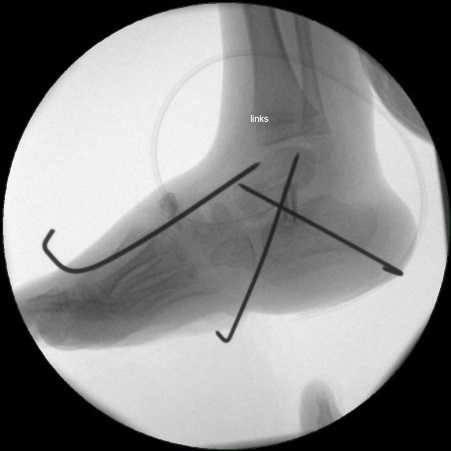

• Röntgenkontrolle (Bild 21,22).

• Im dargestellten Fall war zusätzlich eine plantarflektierende Cuneiforme mediale Osteotomie mit resorbierbarem Knochenersatz und eine Wadenmuskeldissektion nach Vulpius durchgeführt worden.

• Stabilisierung des Spanes mit Kirschnerdrähten (Bild 18).